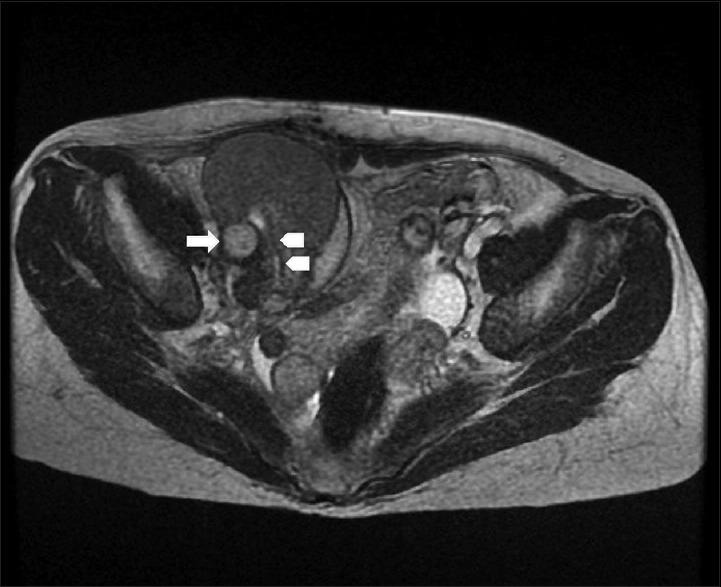

Vascular complications are serious problems after kidney transplantation. An aneurysm or rupture in a graft artery is a rare but potentially devastating complication, which may lead to renal function impairment, graft loss, or even death. In this paper, we present two rare vascular complications in the early postoperative course after renal transplantation from the same deceased donor. In the first case, a 49-year-old woman who had spontaneous graft arterial rupture 13 days after kidney transplantation presented with sudden distension in the right lower abdomen. In the second case, a 56-year-old woman recipient with a graft renal arterial pseudoaneurysm presented with decreased urine output and deteriorating renal function 32 days after transplantation. Immediate surgical repair was performed, and fibrin sealant was applied to strengthen the fragile renal arterial wall. Although the function of both graft kidneys recovered well after surgery, the first graft kidney was removed 2 months later because of repeated fungal and bacterial infections. Aggressive surgical reconstruction may preserve graft kidneys in patients with vascular complications after kidney transplantation, but recovery of the graft condition remains a demanding challenge in renal transplantation.

血管并发症是肾移植术后的严重问题。移植肾动脉的动脉瘤或破裂是一种罕见但可能具有毁灭性的并发症,可能导致肾功能损害、移植肾丧失,甚至死亡。在本文中,我们呈现了来自同一已故供体的肾移植术后早期出现的两例罕见血管并发症。第一例中,一名49岁女性在肾移植术后13天出现移植肾动脉自发性破裂,表现为右下腹突然膨隆。第二例中,一名56岁女性受者在移植术后32天出现移植肾动脉假性动脉瘤,表现为尿量减少和肾功能恶化。立即进行了手术修复,并应用纤维蛋白密封剂加固脆弱的肾动脉壁。尽管两个移植肾在术后功能恢复良好,但由于反复发生真菌和细菌感染,第一个移植肾在2个月后被切除。积极的手术重建可能使肾移植术后出现血管并发症的患者保留移植肾,但移植肾状况的恢复在肾移植中仍然是一项艰巨的挑战。